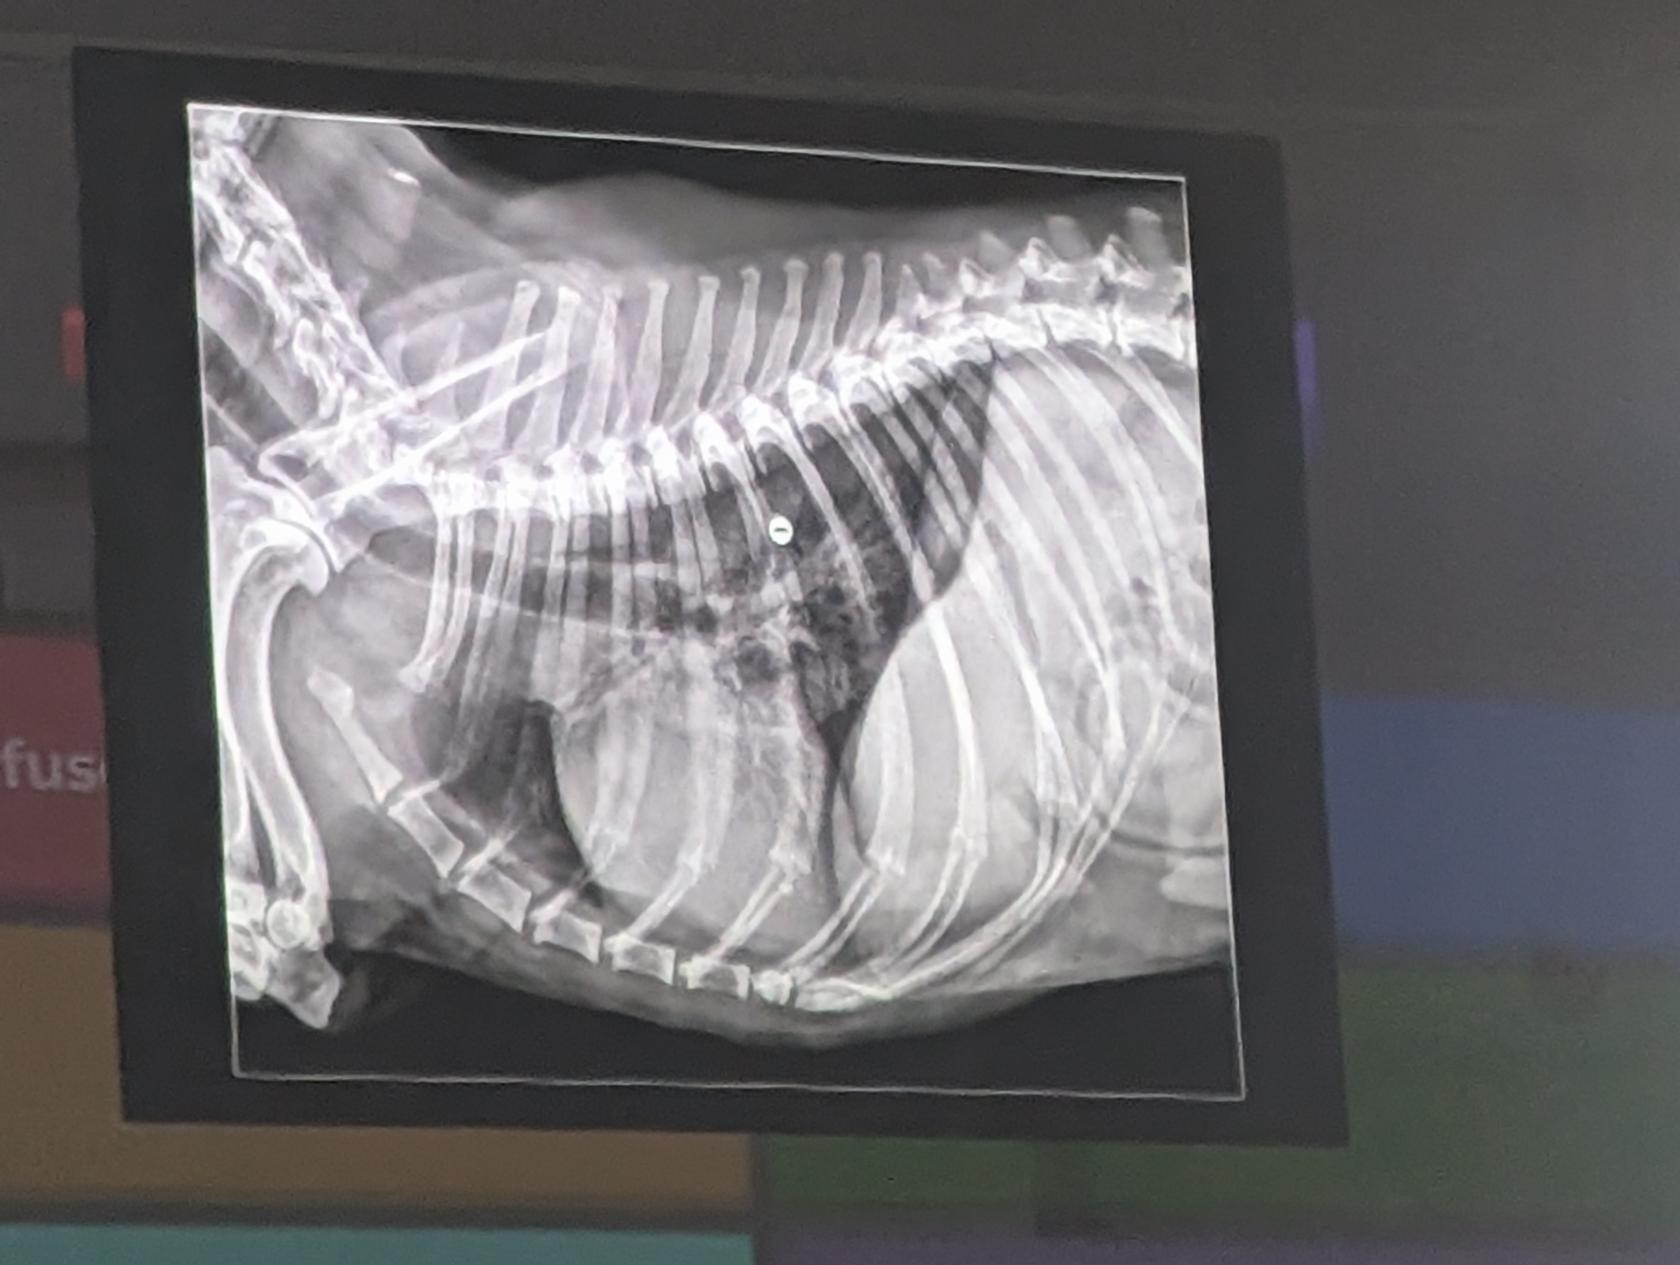

- Hay un desplazamiento dorsal del piloro (por torsion estomacal)

- Signo de doble burbuja ( presencia de dos compartimentos llenos de gas en el estómago por el giro, el cual aparece distendido y rotado.)

- Torsión Gastrica

- Hay una dilatación gastrica (por torsión)